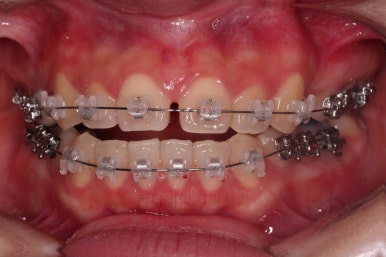

우선 장치를 부착했습니다.

이번에 선택한 장치는 엠파워 클리어라고 하는 자가결찰 세라믹 장치인데요.

흔히 아시는 클리피씨 장치와 같은 분류의 장치입니다. 클리피는 일본, 엠파워는 미국 제조사라는 차이가 있지만 큰 틀에서는 세라믹 바디에 금속 클립이 달린 거의 동일한 장치라고 보시면 됩니다.

장치 부착 직후의 모습인데요.

장치가 보이는 느낌이나 옆라인의 변화 양상은 참고해 주세요.